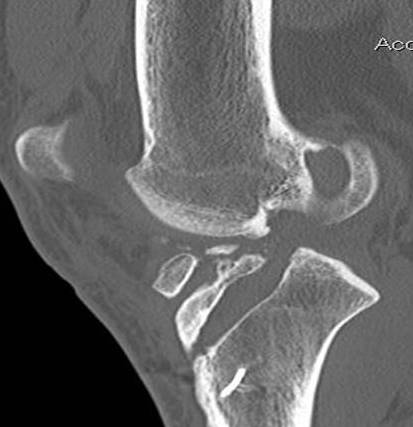

Coronal MRI can see ACL stump remnant, graft not intact. First sagittal confirms tunnel lysis.

Second demonstrates that femoral tunnel is sufficiently posterior